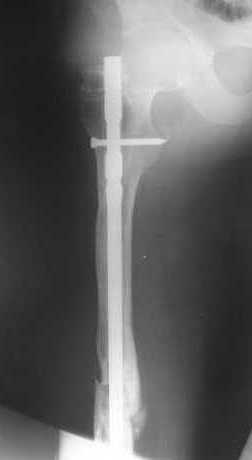

Как обещал, выкладываю рентгенограммы нашего пациента.

Пациенту М., 30-ти лет, 1,5 года назад в одной из московских больниц был выполнен остеосинтез бедренной кости штифтом UFN (диаметр штифта 9 мм).

К нам больной поступил с признаками ложного сустава бедренной кости, перелома

штифта и дистального блокирующего винта (images 1,2,3).

27 марта выполнено удаление блокирующих винтов (сломанный винт пришлось высверливать цапфен-бором), сломанного штифта (дистальный фрагмент удален через канал, образованный разверткой из коленного сустава - image 4),

рассверливание костно-мозгового канала, реостеосинтез штифтом UFN (при проведении штифта в дистальном отломке мы использовали поляризующий винт, диаметр штифта 10 мм). После операции в связи гемартрозом дважды (на 1 и 3 сутки) выполняли пункцию коленного сустава. Сейчас признаков скопления жидкости в полости сустава нет. Послеоперационные рентгенограммы - images 5, 6, 7.